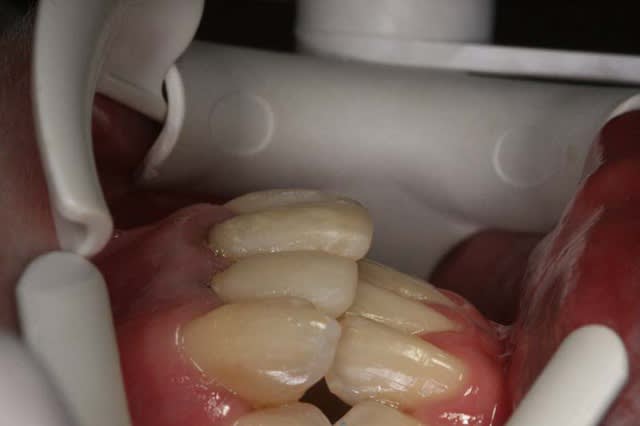

Voici le cas il y a 8 jours, c.a.d. 1 an et 1 mois après les photos de son dernier rendez vous

entre temps, elle est allée se faire faire des provisoires sur 12/11 par un confrère plus prés de son domicile

voici le résultat de l’absence de contention, qui aurait été (a mon avis) une erreur compte tenu que le cas n’était pas terminé

c’est mal foutu, c’est déglingué mais je n’ai aucune malposition Inc. Inf.

c.a.d. : AUCUNE RECIDIVE D’ENCOMBREMENT AVEC ROTATIONS

les dents ne sont pas alignées, mais j’ai mon espace globale, je peux poursuivre ce traitement avec sérénité

Le jeune confrère lui a dit avoir réalisé les provisoires de 12/11 en supra-gingival pour laisser la gencive redescendre, mais il n’a pas rectifié le surbombé des dents provisoires du commerce

ce que j’ai fait, on verra bien à la prochaine consultation